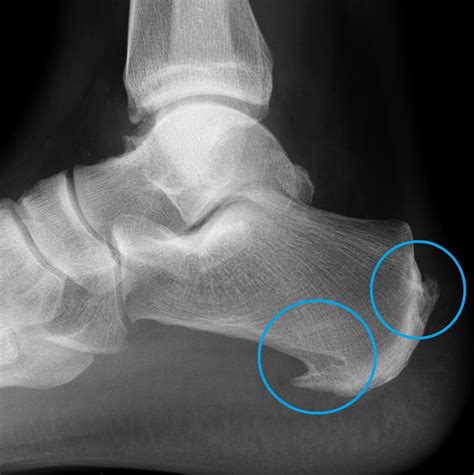

• X-Rays: X-rays can reveal the presence of bone spurs and provide information about their size and location.

Bone Spurs in the Foot

Foot bone spurs, particularly in the heel, can cause significant pain and discomfort. Plantar fasciitis is a common cause of heel spurs. Treatment options include rest, ice, orthotics, physical therapy, and in some cases, surgery to remove the spurs.